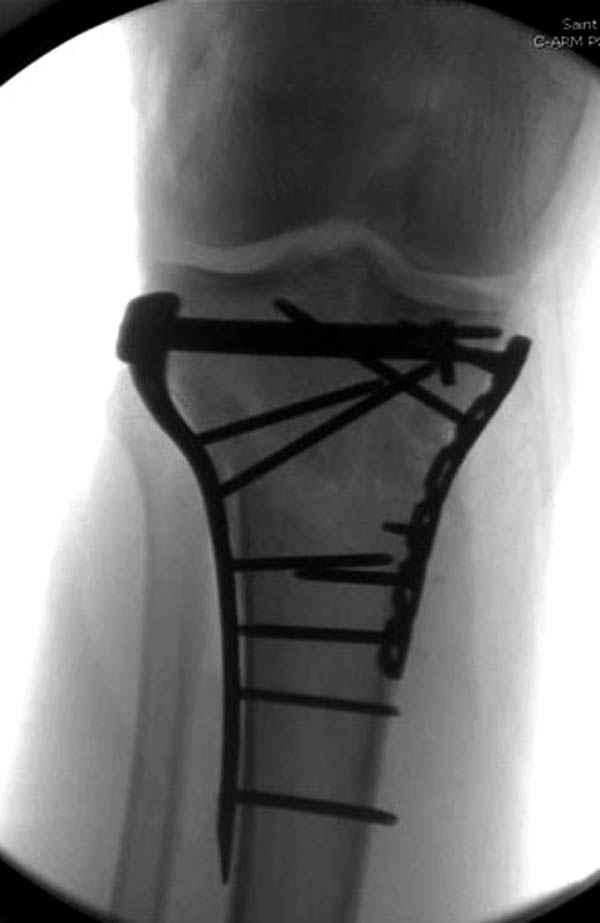

Трудно поверить, что разрекламированная Ортопедическая школа Восточной Украины позволяет такие странные снимки? На прямом снимке сохранен общий контур плато, но не известна судьба импрессии суставной поверхности. На полубоковой?, оставлен без репозиции задне-медиальный отдел, и навряд ли после такой фиксации можно удовлетвориться результатом.

Такая ситуация характерна для многих, когда принимается ошибочное решение, т.е пытаются фиксировать одним имплантом переломы двух мыщелков. Латеральная пластина приемлема только для тех случаев, когда сохраняется интактным медиальный диафизарный кортекс и отсутствует фрагментация на верхушке медиального перелома.

Представленные снимки не информативны, нужны отдельные качественные снимки коленного сустава и голени без ротации.